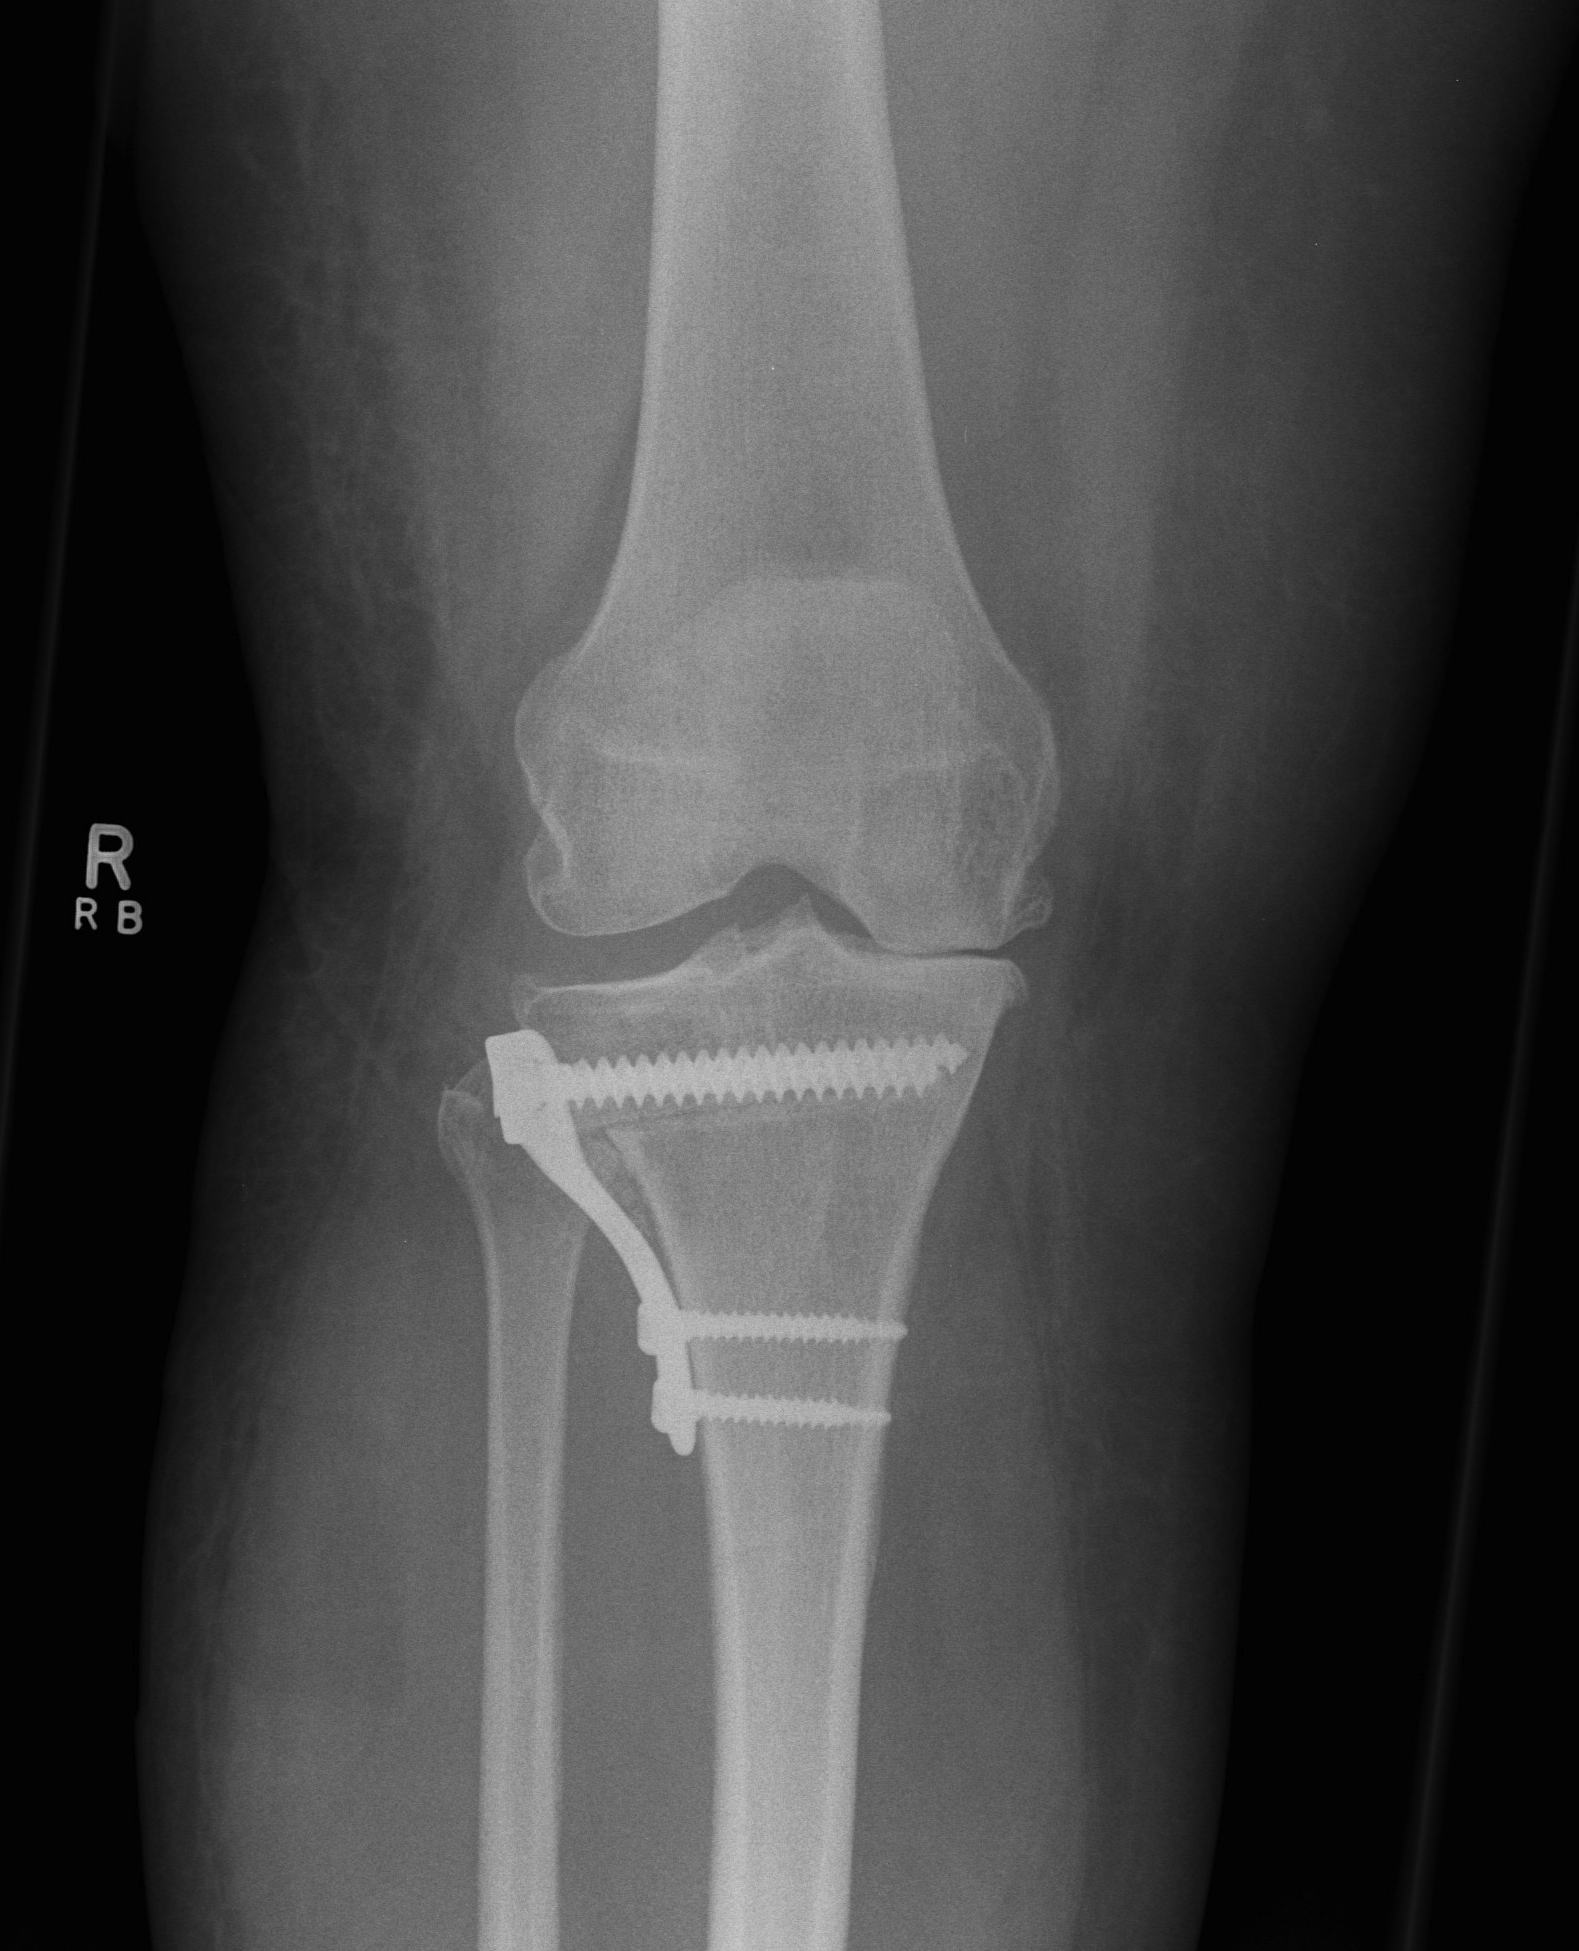

Difference between closed wedge high tibial osteotomy CWHTO a b best sale, High tibia osteotomy. a with closing wedge b with opening best sale, A closing wedge proximal tibial osteotomy. Download Scientific best sale, Knee Osteotomy Saint Luke s Health System best sale, Technique Closing Wedge The Bone School best sale, Medial closing wedge high tibial osteotomy for valgus tibial best sale, Technique Closing Wedge The Bone School best sale, Truffle Collection wide fit closed toe wedges in black ASOS best sale, Buy Women s Closed Toe Wedges Famous Footwear Australia best sale, Lateral Closing Wedge Osteotomy Musculoskeletal Key best sale, ASOS DESIGN Wide Fit Tyra closed toe wedges in natural linen ASOS best sale, Soda Black Closed Toe Wedge Heels Black heels wedges Black best sale, Closed Toe Wedge Sandals Tan Women s Shoes Monsoon Global best sale, Hitomi espadrille woven closed toe 8cm wedge heel sandals denim blue best sale, Vionic Anna Closed Toe Wedge Sandal Free Shipping Returns best sale, Tommy Hilfiger BASIC CLOSED TOE MID WEDGE Black Fast delivery best sale, Full Closed Wedge Heel Black best sale, Closed Toe Wedge Sandals Tan Women s Shoes Monsoon Global best sale, Lateral Closing Wedge Osteotomy Musculoskeletal Key best sale, Wedge Sandals Black Closed Toe Stiletto Heel PU Leather Black best sale, TUOBARR Wedge Platform Sandals Women s Closed Toe Buckle Strap best sale, ASOS DESIGN Wide Fit Treasure closed toe wedges in natural fabric best sale, Closed toe Slingback Wedge 10609 Aerosoft best sale, Madison Cleo Closed Toe Espadrille Wedge Navy Madison Heart of best sale, Wedges Sandals Shoes High Heel Hessian Cushioned Ladies Closed Toe best sale, Amazon mysoft Women s Wedge Pumps Closed Toe Low Heel Dress best sale, Cranial Tibial closing Wedge Osteotomy CTWO with patient specific surgical guides best sale, Women s Espadrille Wedge Heels Closed Toe Ankle Strap Temu best sale, Comparison between conventional and hybrid closed wedge high best sale, WHITE WEDGE HEELS Leather Heels Ankle wrap Sandals White best sale, Amazon Ruanyu Womens Platform Espadrilles Wedge Sandals Slip best sale, Froggie 10572 Closed Wedge in French Featherbys best sale, Closed Toe Wedge Sandals Tan Women s Shoes Monsoon Global best sale, Closed toe wedge sandal in beige lace by Refresh Isabel s Retro best sale, Closed Wedge Socket De Haan Special Equipment best sale, amlbb Womens Wedge Sandals Closed Toe Wedges Shoes Platform best sale, Wonders Closed Toe Wedge Sandals Silver 6703 The Shoe Horn best sale, Talitha closed Black Wedge Charming Shoes South Africa best sale, Closed Toe Wedges Shop Closed Toe Wedges Macy s best sale, Closed Toe Wedges Etsy best sale, Closed toe Slingback Wedge 10609 Aerosoft best sale, Heels Rumor Closed Toe Wedges Dorothy Perkins best sale, Franco Rossi Allison Closed Back Wedge Black Shoe Box Online best sale, Closed Wedge Sockets CWS RopeBlock best sale, Westlyn Closed Toe Wedge Sustainable Shoes Reformation best sale, Office High Heel Wedge Pumps Closed Toe Slip on Shoes for Work best sale, Lateral femoral closing wedge osteotomy in genu varum ScienceDirect best sale, Sensational Black Closed wedge Order from Rikeys faster and cheaper best sale, Lace Up Ankle Closed Toe Jute Trim Wedges Closed toe espadrilles best sale, Tibial Osteotomy with Closed Wedge best sale.

Medial closing wedge high tibial osteotomy for valgus tibial

Lateral Closing Wedge Osteotomy Musculoskeletal Key